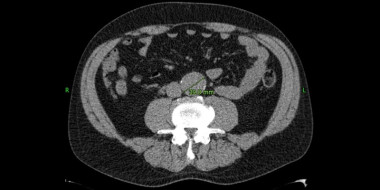

AAA: (hoog) tijd voor screening

Een aneurysma van de aorta abdominalis (AAA) is een aandoening die over het algemeen asymptomatisch verloopt, totdat er een ruptuur optreedt. De prevalentie ligt tussen de 4 en 9%, de aandoening komt voornamelijk voor bij mannen van 65 jaar en ouder. Voor een normpraktijk van…